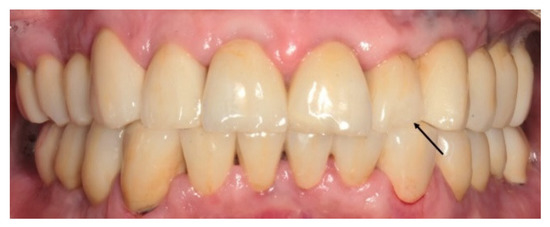

2. Materials and Methods

2.4. Methods